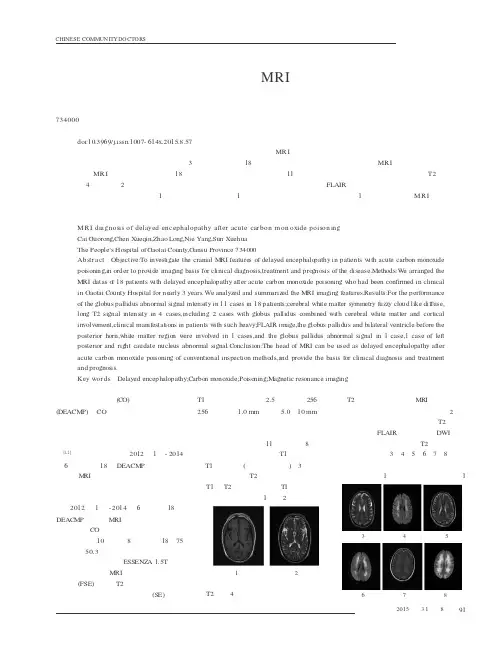

论著临床辅助检查CHINESE COMMUNITYDOCTORS中国社区医师5年第3卷第期急性一氧化碳(CO)中毒迟发性脑病(DEACMP)是CO 中毒患者经抢救在急性中毒症状恢复后经过一段时间的正常或者接近正常状态的时期后,又复出现以急性痴呆为主要表现的一组神经精神症状[1-2]。

本研究分析我院2012年1月-2014年6月收治的18例DEACMP 患者的临床资料及M RI 特点,现报告如下。

资料与方法2012年1月-2014年6月收治18例DEACMP 患者的MRI 资料,均符合《职业性急性CO 中毒诊断标准及处理原则》。

其中男10例,女8例,年龄18~75岁,平均50.3岁。

扫描方法:采用ESS ENZ A 1.5T 超导型磁共振仪进行MRI 检查,使用快速自旋回波(FSE)序列,T2加权像行横断、冠状、矢状面扫描,以自旋回波(S E)序列,T1加权像。

采集次数2.5次,矩阵256×256,厚间距1.0mm ,层厚5.0~10mm 。

结果苍白球异常信号11例,其中8例双侧苍白球对称性斑片状长T1信号灶,有短T1信号环绕(提示胶质增生),3例分别为双侧苍白球长T2信号灶,双侧苍白球长T1长T2信号灶,有短T 1信号环绕,提示胶质增生,见图1和图2。

图1图2脑白质对称性的弥漫、模糊云雾状长T2信号4例,表现为双侧脑室旁片状长T2信号,对称分布;MRI 显示苍白球合并脑白质受累者及皮层受累者2例,病情较重,双侧脑室旁片状长T2信号,对称分布,FLAIR 呈高信号,DWI 弥散受限,双侧脑白质弥漫长T2信号,部分皮层受累,见图3、4、5、6、7、8。

双侧苍白球及双侧脑室前、后角旁白质区均受累1例,并苍白球异常信号1doi:10.3969/j.issn.1007-614x.2015.8.57摘要目的:探讨急性一氧化碳中毒迟发性脑病患者的头颅MR I 表现,为该病的临床诊断、治疗和预后提供影像学依据。